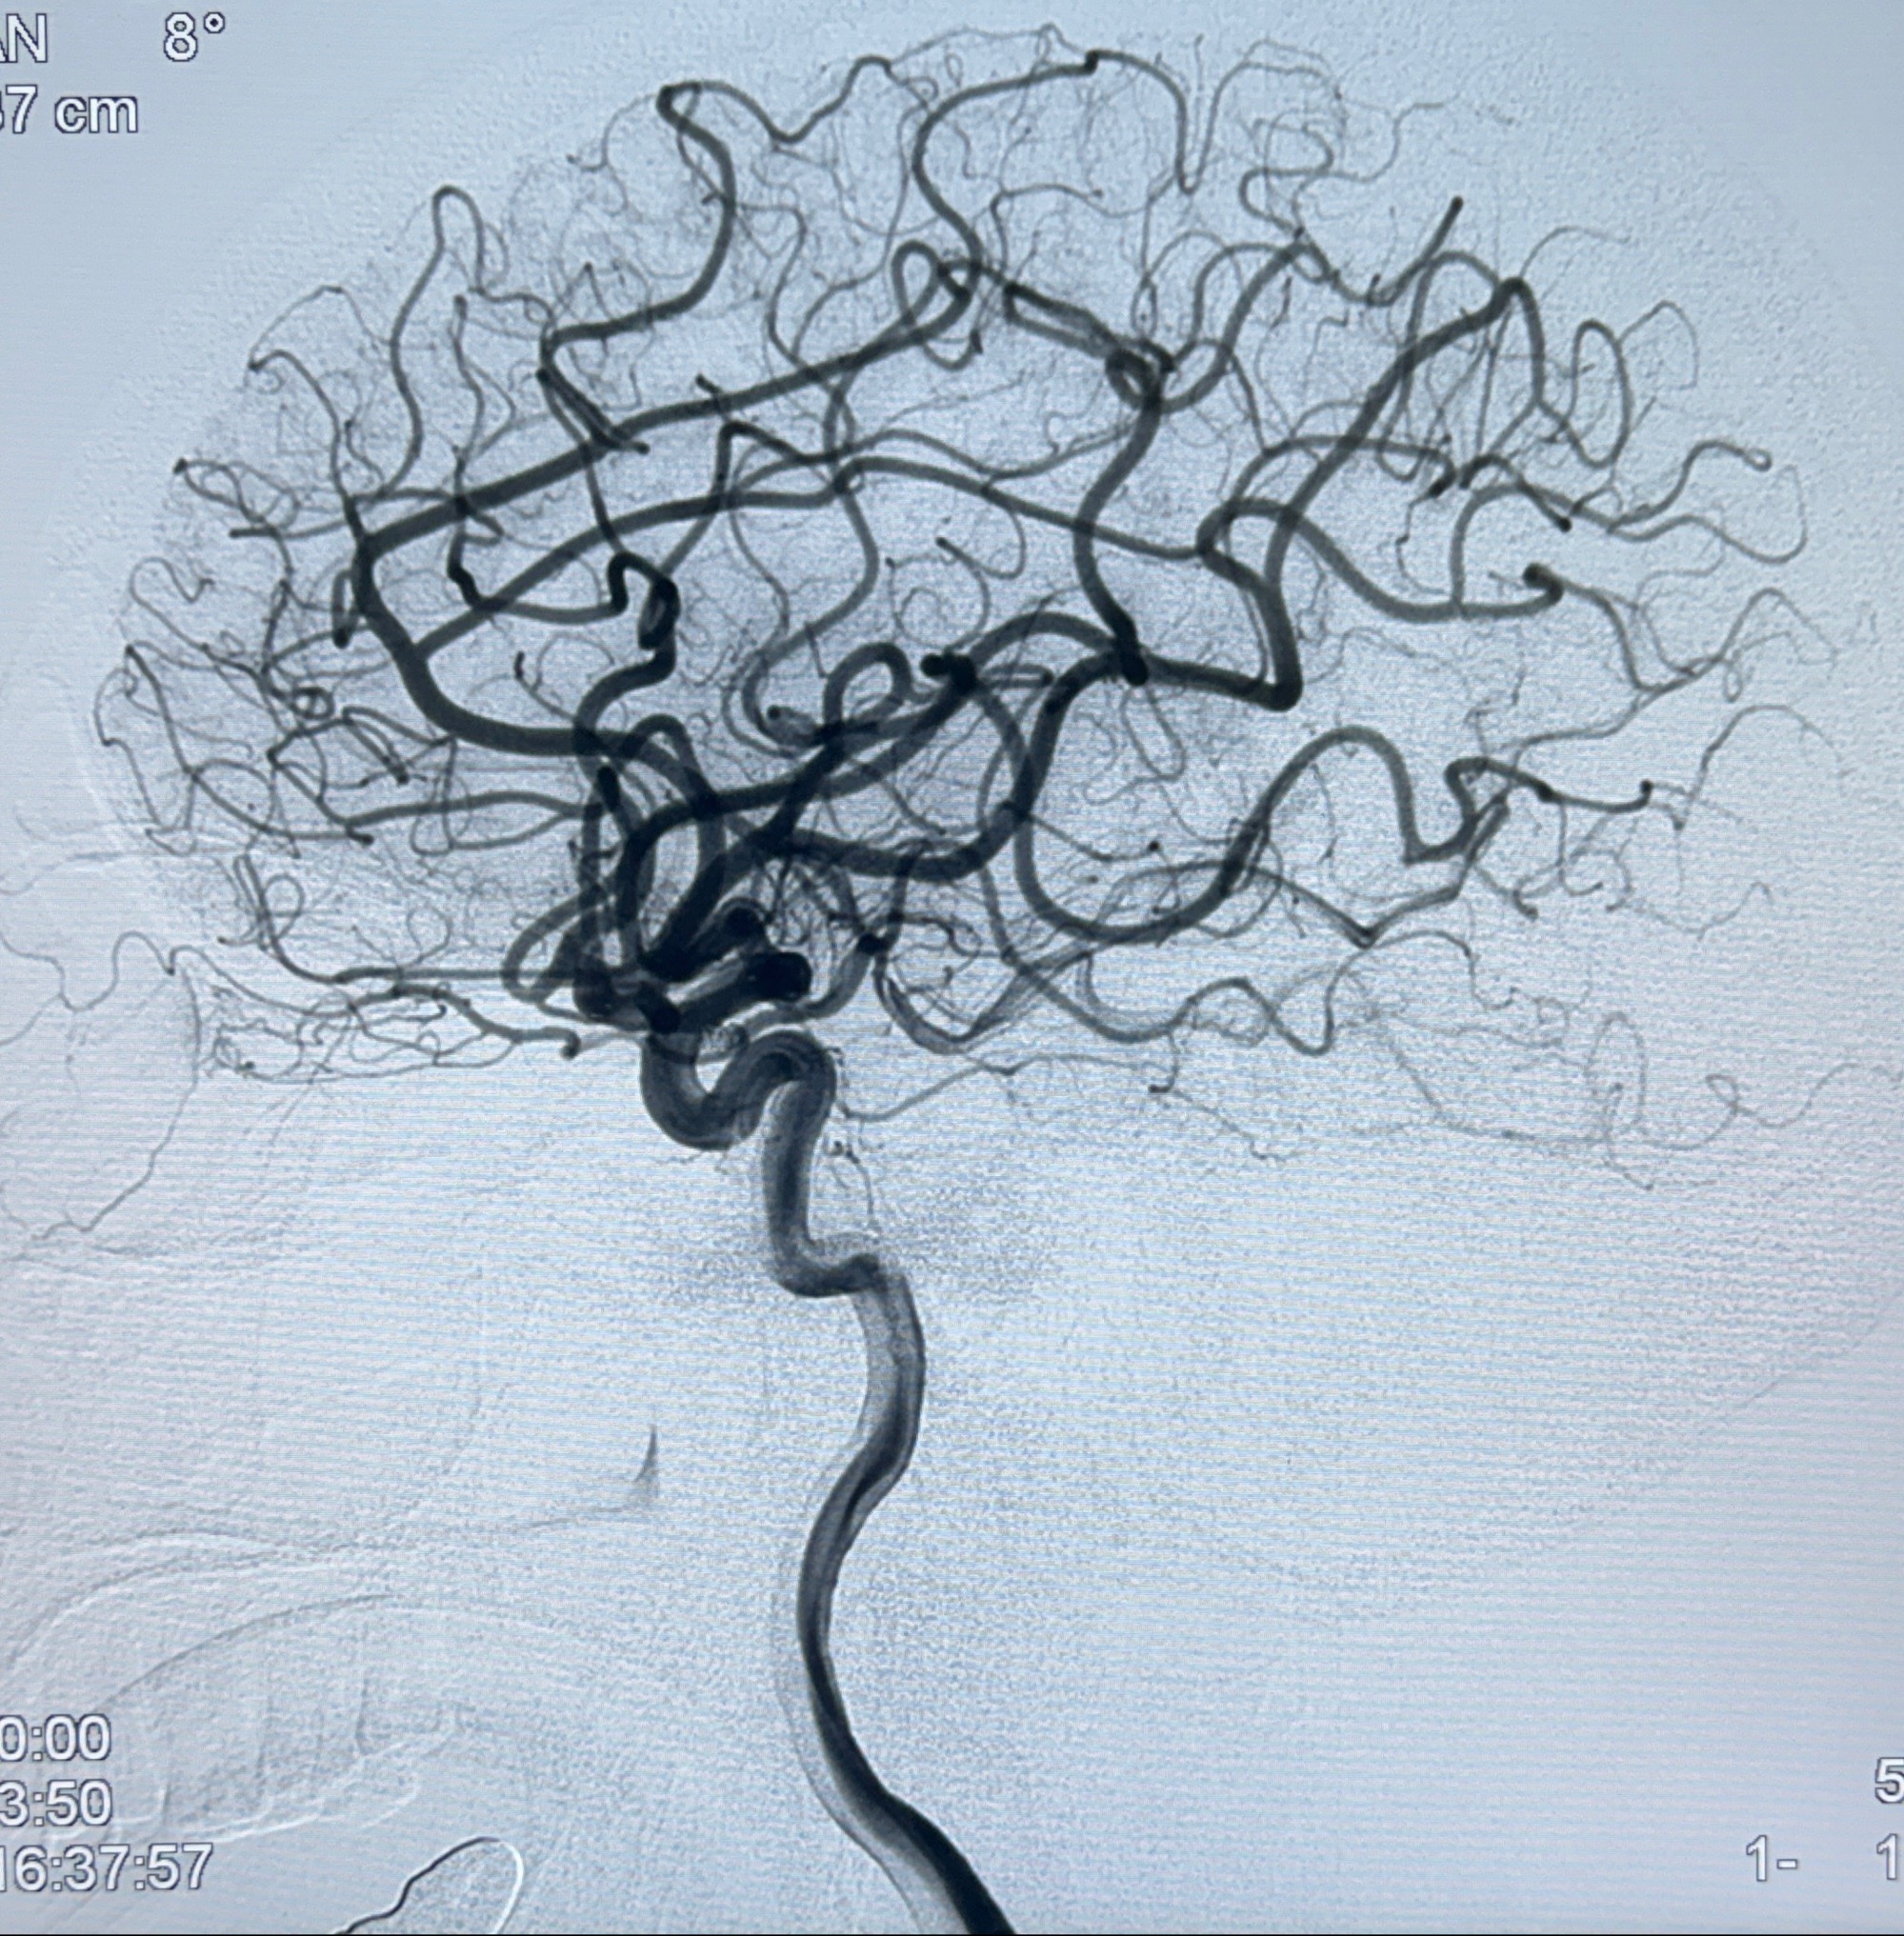

2023-11-24DSA:右侧大脑中动脉下干起始部动脉瘤,约2.3*2.5mm,形态规则

2023-12-04全麻下行支架辅助治疗

S-AB4-20mm